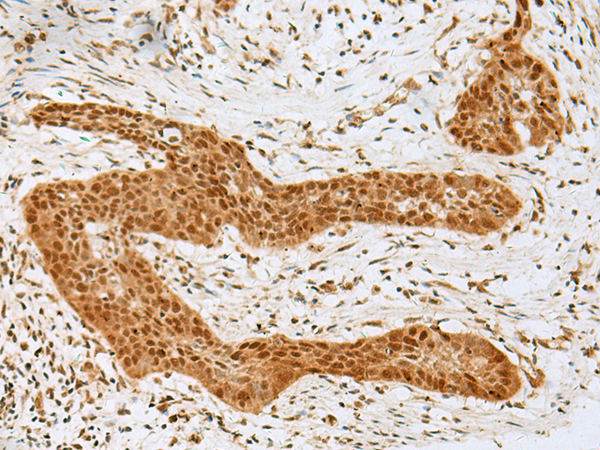

IHC positive control: |

Human thyroid cancer |

IHC Recommend dilution: |

40-200 |